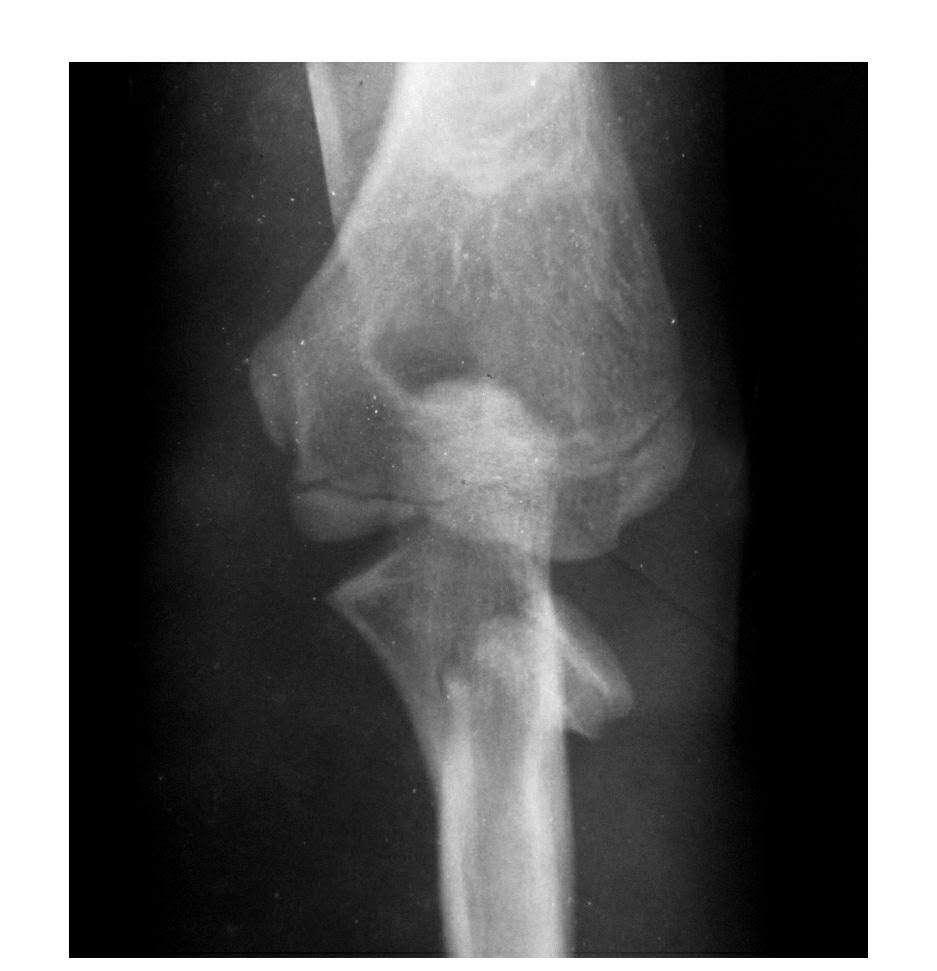

(二)部分骨折

本病亦称科-洛(Kocher-Lorenz)型骨折

例1:肱骨小头软骨面及其下方少量骨质呈“新月样”被剥脱,且向肘前上方移位并桡骨头前半部骨折。

例2:肱骨小头软骨面剥脱性骨折,致该小头新月状骨片被向前脱位的桡骨头顶向肘关节前上方,并尺骨干中段骨折(孟氏伸展型骨折)。